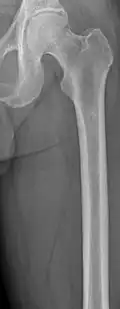

Bone pain affects almost 70% of people with multiple myeloma and is one of the most common symptoms.[2]: 653 [23] Myeloma bone pain usually involves the spine and ribs and worsens with activity. Persistent, localized pain may indicate a pathological bone fracture. Involvement of the vertebrae may lead to spinal cord compression or kyphosis. Myeloma bone disease is due to the overexpression of receptor activator for nuclear factor κ B ligand (RANKL) by bone marrow stroma. RANKL activates osteoclasts, which resorb bone. The resultant bone lesions are lytic (cause breakdown) in nature. They are best seen in plain radiographs, which may show "punched-out" resorptive lesions (including the "raindrop" appearance of the skull on radiography). The breakdown of bone also leads to the release of calcium ions into the blood, leading to hypercalcemia and its associated symptoms.[24]

The diagnostic examination of a person with suspected multiple myeloma typically includes a skeletal survey. This is a series of X-rays of the skull, axial skeleton, and proximal long bones. Myeloma activity sometimes appears as "lytic lesions" (with local disappearance of normal bone due to resorption) or as "punched-out lesions" on the skull X-ray ("raindrop skull"). Lesions may also be sclerotic, which is seen as radiodense.[76] Overall, the radiodensity of myeloma is between −30 and 120 Hounsfield units (HU).[77] Magnetic resonance imaging is more sensitive than simple X-rays in the detection of lytic lesions. An MRI may supersede a skeletal survey, especially when vertebral disease is suspected. Occasionally, a CT scan is performed to measure the size of soft-tissue plasmacytomas. Nuclear Medicine Bone scans are typically not of any additional value in the workup of people with myeloma (no new bone formation; lytic lesions not well visualized on nuclear bone scan).